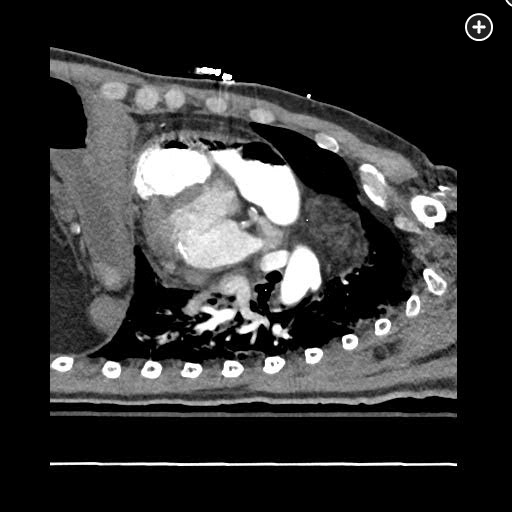

The CT pulmonary angiogram demonstrates a large volume of air in the right atrium, ventricle, and pulmonary outflow tract, with leftward bowing of the interventricular septum, suggestive of acute right heart strain (Figure 1, Figure 2, Figure 3, Figure 4).

Sagittal CT image better demonstrating a massive air embolism involving the right ventricle and pulmonary outflow tract.